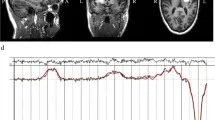

Рисунок 1

Рисунок 2

Рисунок 3